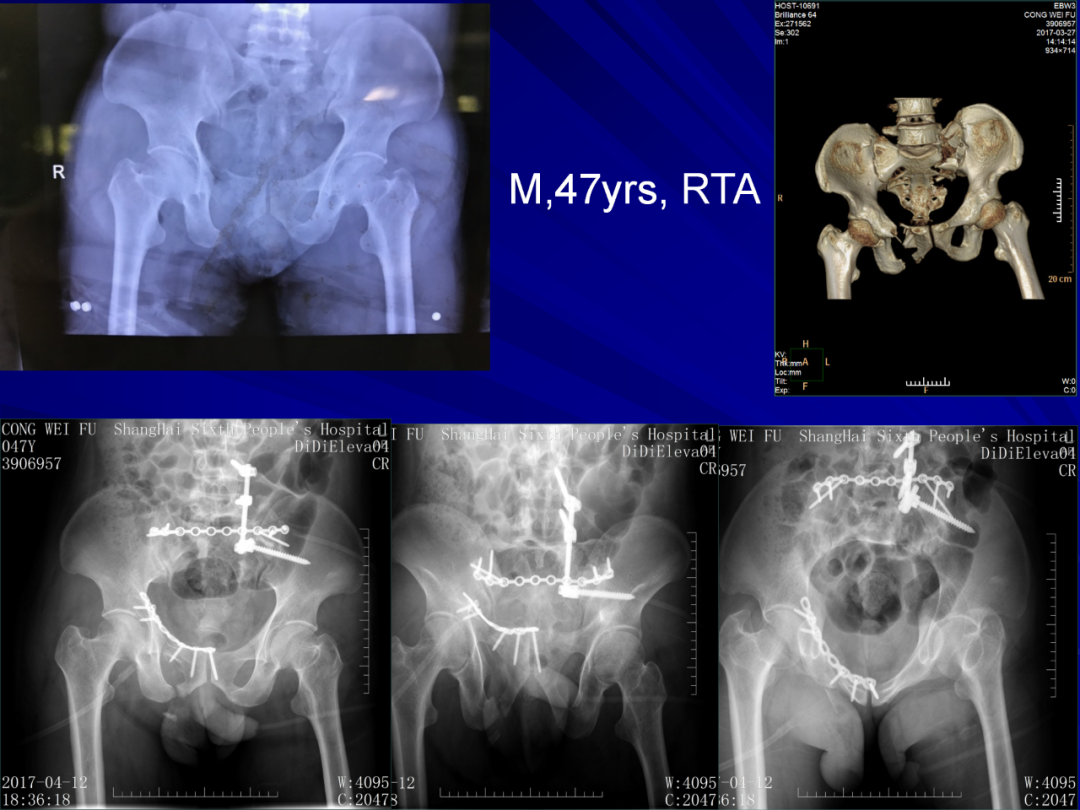

364例复杂骨盆骨折带你掌握内固定技术!